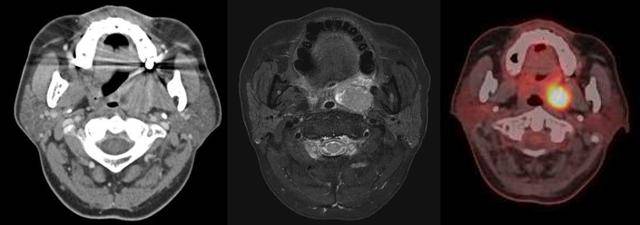

목과 편도가 붓고 구강 뒤쪽의 통증을 호소하며 병원을 찾는 환자들 중 구강암을 걱정하며 찾아오시는 분들이 있습니다. 대부분은 염증성이지만, 구인두암의 경우에는 신체 검진만으로 악성을 완전히 배제할 수 없는 경우가 많기 때문에 CT나 MRI와 같은 영상의학적인 검사 및 조직검사가 필요할 수 있습니다.

또한, 일반적인 절개 수술과 경구강 로봇수술, 방사선치료, 항암치료 등 다양한 치료방법이 있고, 종양의 종류와 위치, 병기에 따라 다양한 순서와 조합으로 치료를 해야 합니다. 따라서 환자 개개인에 적합한 맞춤형 다학제(여러 진료과가 함께 하는) 치료가 필요한 종양입니다.

구인두암은 종양의 위치와 병기에 따라 다소 차이는 있지만, 방사선치료와 수술의 치료 효과가 비슷합니다. 방사선치료는 치료 장비와 치료 기법의 발달로 치료가 필요한 부위에 방사선량을 최대한 집중하고 정상 부위에는 최소한으로 들어가도록 발전해왔습니다.

특히 조기암(1기, 2기 암)에서는 경구강 수술이 정상 조직을 최대한 보존하면서 암을 제거해 정확한 병기를 파악하고 추후 예후 판단이나 추가 치료를 결정할 수 있어 각광을 받고 있습니다. 진행된 암(3, 4기암)에서는 방사선치료와 항암치료를 병행하거나, 수술 후 보조적 방사선 치료를 시행해야하는 경우가 많습니다.